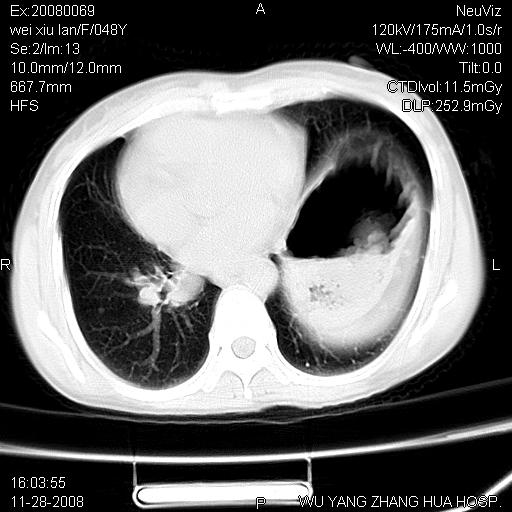

标题: CT16847:女,48岁,咳嗽,发热两日,平常偶有上腹部不适。 [打印本页]

标题: CT16847:女,48岁,咳嗽,发热两日,平常偶有上腹部不适。

能否考虑食管裂孔疝?请老师们多多指教。

这个是左侧膈膨升伴不完全性胃翻转,手术将松弛的左横膈膜折叠缝合即解决问题。

支持左侧膈疝,心脏受压右移.

左下肺不张、膈膨升,胸腔胃

胃、脾脏及部分肠管明显升高,并压迫心脏移位,

首先考虑:左侧膈疝。

左侧胸腔内见胃肠及脾脏影

支持膈疝

左膈顶及肋膈角均上移,膈面光滑,考虑左膈肌麻痹